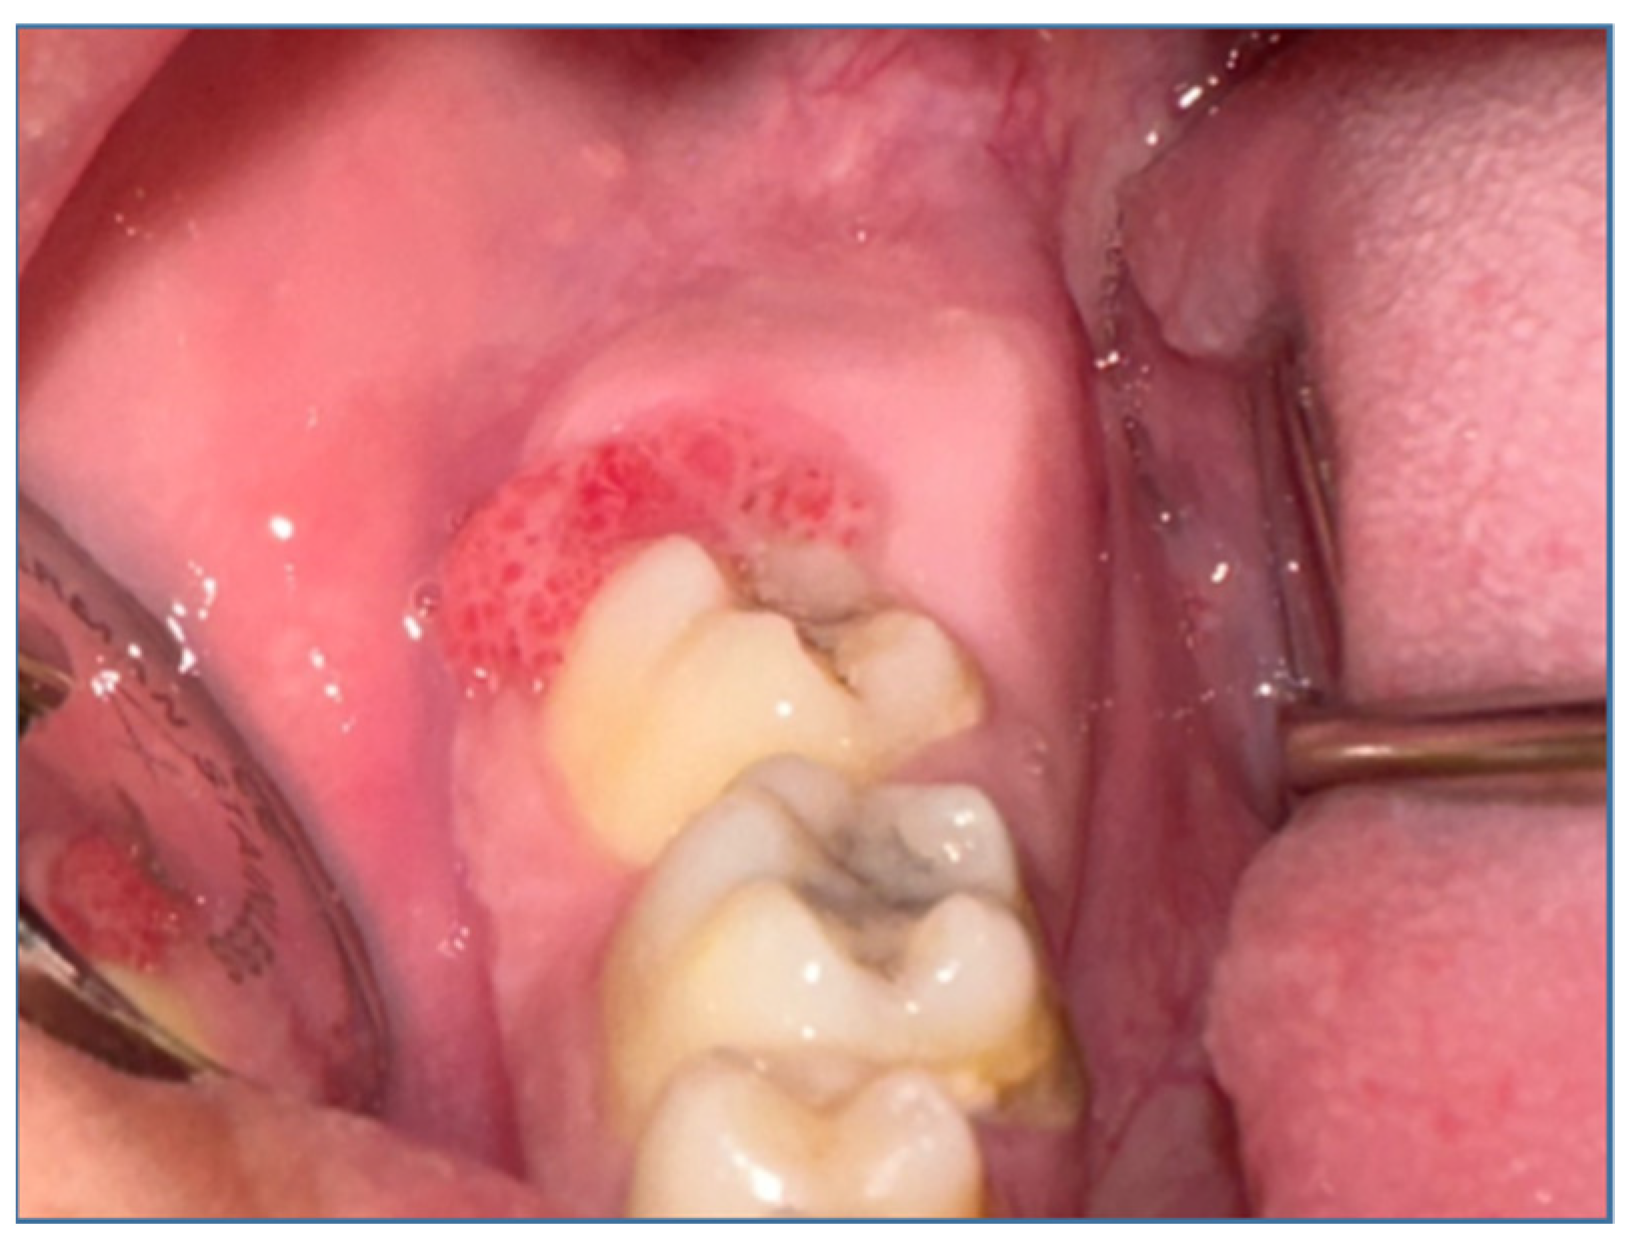

The facial examination (Figure 1) showed an asymmetry caused by a large diffuse swelling located in the right mandibular region, hard in consistency and painless. The skin overlying the swelling was stretched and was of normal color. The swelling started spontaneously and gradually increased to its current size. There was no history of trauma or dental pain. The patient was experiencing pain while chewing and did not have altered sensation over the right lip region. The intraoral examination (Figure 2) revealed a swelling in the right lower posterior buccal vestibule extending from the second premolar to the retromolar region. The overlaying mucosa presented a superficial ulceration distal from the second molar. The laboratory tests, consisting of a complete blood count and biochemical and coagulation profiles, were all within normal limits. The only test that showed increased values was ESR = 24 mm/h (0–10 mm/h). Also, the procalcitonin (PCT) value was slightly increased at 0.41 (0.17–0.35/fL). This showed a degree of superinfection. The interdisciplinary cardiological consultation, including the EKG, did not show any changes. The chest X-ray showed no changes. No cervical ultrasound was performed, the cervical ganglion system being clinically unchanged.

Figure 2. Intraoral examination.